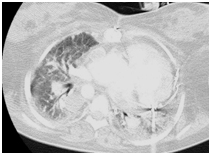

COVID-19 contamination was confirmed on March 16th, rapidly evolving to orotracheal intubation on March 17th. Continuous hemodialysis and vasoactive drugs (adrenaline and milrinone) were again needed. Lung computerized tomography confirmed more than 50% lung affected by SARS-CoV-2, and patient evolved in need of prone positioning.

Figure 2 Tomographic aspect demonstrating pulmonary involvement by Covid 19 on March 19, 2021.

Figure 3 Tomographic aspect demonstrating pulmonary involvement by Covid 19 on April 4, 2021.